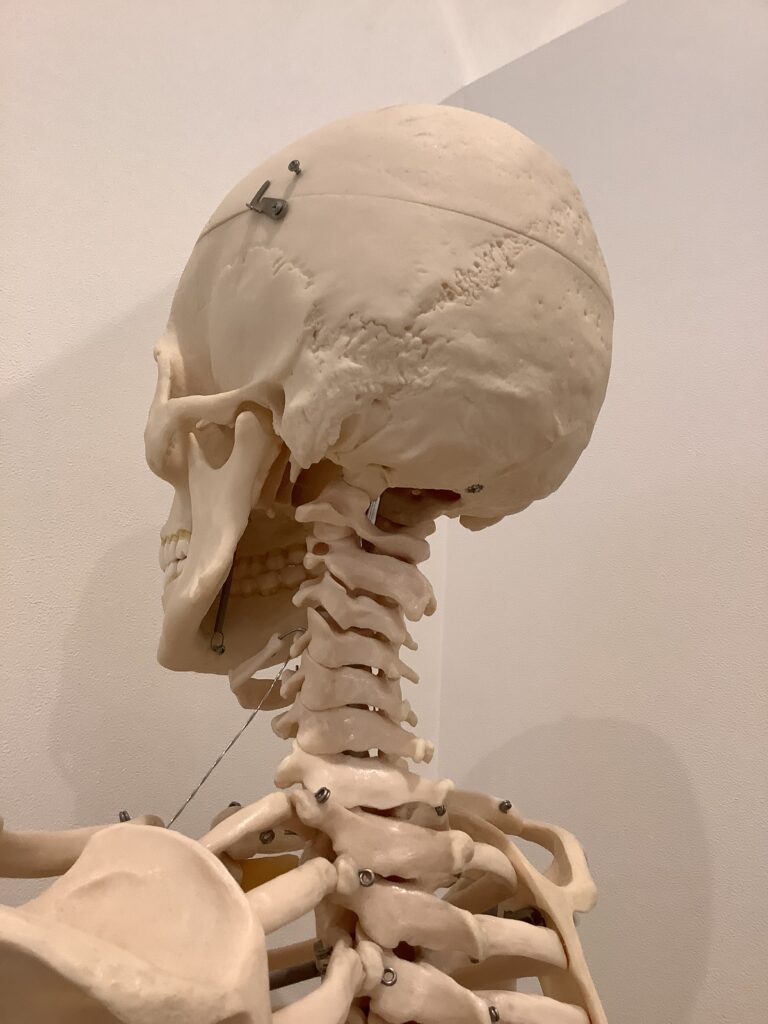

首に強い張りやコリを感じている方に共通する歪みは、首にある頚椎、背骨の胸椎が後弯いわゆる猫背となり、顔だけが前に出ている状態です。また、頭の頭蓋骨のうちの後頭骨が下方へ下がり、頭の後ろにある大後頭直筋などの筋肉がガチガチに硬い状態になっている方が多いです。首の不調をそのまま放っておくと、硬くなった筋肉がより首の骨格を歪ませるため、痛みや首の可動域等の不調も引き起こします。さらには、首とつながっている背中や肩の不調にもつながるケースは多くあります。

マッサージで改善されない首の不調は根本の骨格の調整から。頚椎や胸椎を整え筋肉を緩めやすくする土台を作りましょう。骨格の歪みを検査する骨格ドックと骨格の調整がセットになったメニューは、こちらからご覧ください。